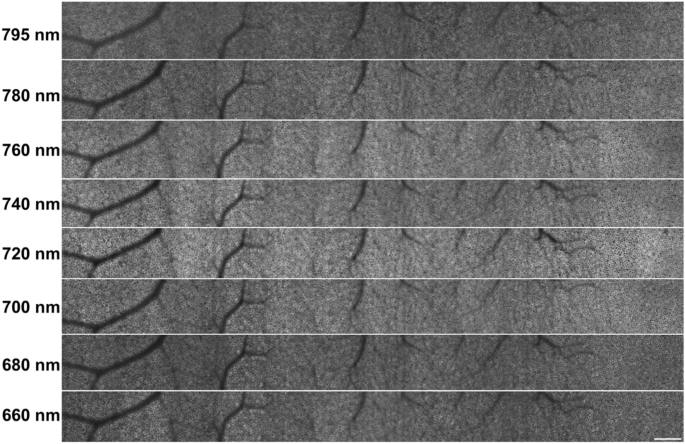

Imaging protocol. All participants were imaged using center wavelengths of 660, 680, 700, 720, 740, 760, 780, and 795 nm. For each excitation wavelength, different sets of dichroic mirrors and filters were used (shown in Table 1).

The montages of the RPE cells from a 20 year old (y.o.) female, from the fovea to \(12^{\circ }\) temporal, can be seen in Fig. 4. The fovea is positioned on the right of the montages. The RPE cells in the montages appeared with a hyper-fluorescent border and a hypo-fluorescent center. Qualitatively, the contrast and intensity of the RPE cells varied across wavelength. The RPE cells appeared more defined around the fovea and towards \(12^{\circ }\) temporal whereas the RPE cells appeared noisier in the intermediate eccentricities (\(\sim\) \(6^{\circ }\)temporal). This observation was more evident in the 795 and 660 nm montages. Also, intermediate wavelengths had higher contrast and brightness compared to the longest and shortest wavelengths tested. Additionally, the longer wavelengths resolve some RPE cells that lie beneath the blood vessels as longer wavelengths have greater penetration through the blood compared to the shorter wavelengths33.

We quantitatively evaluated the image quality of AOSLO RPE cell images using a previous method45 to determine which imaging wavelength was the most robust for RPE cell imaging. Th is method calculates the signal-to-noise ratio (SNR) in the Fourier domain by differentiating the signal and noise from the radially averaged power spectrum of the 2D Fourier transform. Figure 5a) shows the SNR values across wavelength for the 3 age groups along with the average of all age groups. It was clear that the excitation wavelength that produced images with the highest SNR values was 720 nm, illustrated with a distinct peak at 720 nm for all age groups. Based on the average SNR values of all age groups, the excitation wavelength that produced the highest quality images was 720 nm with 65.0 dB and the worst was 660 nm with 45.0 dB. The SNR value at 720 nm is highest with the young age cohort at 73.9 dB and lowest with the old age cohort at 58.3 dB. There was a gradual decrease in SNR in both directions from the 720 nm peak. Figure 5b) shows the range of SNR values across all age groups when accounting for all imaging wavelengths. The mean SNR value for the young age cohort (56.2 dB) was higher than that of the middle (52.4 dB) and old (47.9 dB) age cohorts. Figure 5c) shows the SNR values across the 3 age groups for images produced with 720 nm only. This comparison was done to compare the image quality across the age groups with the imaging wavelength that produced the highest image quality. The mean SNR value for the young age cohort (73.9 dB) was higher than the middle (63.1 dB) and old (58.3 dB) age cohorts. The middle age cohort had more variance in SNR values with a standard deviation of 14.3 dB compared to the young and old age cohorts with standard deviations of 6.6 and 12.5 dB respectively.